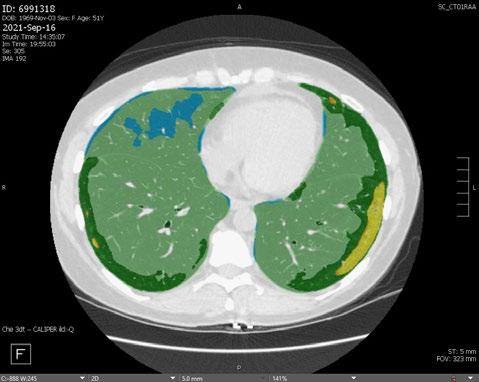

Radiogenomics Relationship of Nonsmall Cell Lung Cancer: Preliminary Results

Citation: EMJ Radiol. 2024;5[1]:24-25. https://doi.org/10.33590/emjradiol/10304578.

BACKGROUND AND AIMS

Radiomics, an emerging paradigm in medical imaging, entails the quantitative analysis of tumour features, and has exhibited potential in predicting treatment responses and outcomes. Furthermore, within the domain of -omics assessments, the significance of comprehensive genetic evaluation in non-small cell lung cancer (NSCLC) is on the rise, influenced by both biological and therapeutic considerations.

The aim of this study was to correlate radiomics features with the genetic results obtained from liquid biopsy in patients with lung tumours. The prediction of tumour genetics in radiomics relies on the presumption of conducting a non-invasive evaluation of molecular characteristics in tumour tissues, which can be challenging in certain tumour types, such as NSCLC. Therefore, in this context, the authors considered it pertinent to explore and generate hypotheses regarding the technical feasibility of identifying associations between genomics acquired through liquid biopsy assessments and radiomics.

MATERIALS AND METHODS

This observational, prospective study integrated radiomic perspectives using CT and genomic perspectives, through next-generation sequencing applied to liquid biopsies.

The authors included 62 patients with NSCLC who underwent pre-surgery CT (Revolution™ 128 MDCT, GE HealthCare, Chicago, Illinois, USA) at the Radiology Department of Campania University Luigi Vanvitelli, Naples, Italy. Every patient for whom liquid biopsy was performed gave informed consent for the genetic analysis. For the radiomic analysis, image processing CT volumes were manually delineated using ITK-SNAP 3.8.0 (University of Pennsylvania, Philadelphia, USA). Radiomics features (first order: Gray Level Co-occurrence Matrix, Gray Level Run Length Matrix, Gray Level Size Zone, Gray Level Dependence Matrix, and Neighbouring Gray Tone Difference Matrix) were computed using Pyradiomics1 in Python 3.7 (Python Software Foundation, USA) environment.

Radiomic features were derived from CT images, and genetic assessments were performed using a comprehensive panel targeting 523 cancerrelated genes. For the statistical analysis, association between radiomic features and gene mutations were assessed using feature importance based on receiver operating characteristic curve analysis; moreover, a machine learning approach based on support vector machine was used to evaluate the ability of radiomic features to predict gene mutations.

Associations between radiomic features and genetic mutations were established using the area under the receiver operating characteristic curve. Machine learning techniques, including support vector machine classification, aimed to predict genetic mutations based on radiomic features. The prognostic impact of selected gene variants was assessed using Kaplan–Meier curves and log-rank tests.

RESULTS

Sixty-two patients underwent screening, with 53 being comprehensively characterised radiomically and genomically. This group was predominantly male (68.4%), and adenocarcinoma was the prevalent histological type (73.7%). Most patients exhibited ECOG Performance Status of 0 or 1 (87.7%), and 91.2% had a history of former or current smoking. Disease staging was distributed across I–II (38.6%), III (31.6%), and IV (29.8%). Significant correlations were identified with mutations

Abstract ● ECR 2024 24 Radiology ● April 2024 ● Creative Commons Attribution-Non Commercial 4.0

of ROS1 p.Thr145Pro (shape_Sphericity), ROS1 p.Arg167Gln (glszm_ZoneEntropy, firstorder_TotalEnergy), ROS1 p.Asp2213Asn (glszm_GrayLevelVariance, firstorder_ RootMeanSquared), and ALK p.Asp1529Glu (glcm_Imc1). Patients with the ROS1 p.Thr145Pro variant demonstrated markedly shorter median survival compared to the wild-type group (9.7 months versus not reached; p=0.0143; hazard ratio: 5.35; 95% confidence interval: 1.39–20.48).

CONCLUSION

This study contributes to advancing the prediction of cancer genetics through the application of non-invasive radiomic techniques. The prediction of tumour genetics in radiomics hinges on the assumption of conducting a non-invasive assessment of molecular characteristics in tumour tissues, which can pose challenges in certain tumour types, such as NSCLC. Therefore, within this context, the authors deemed it relevant to explore and formulate hypotheses regarding the technical feasibility of identifying associations between genomics obtained through liquid biopsy assessments and radiomics.

Specific radiomic features illustrate the capability to predict non-synonymous mutations of ROS1 and ALK in patients with NSCLC. Investigating the prediction of cancer genetics using non-invasive radiomic techniques represents an innovative frontier in scientific research, which is currently undergoing extensive investigation. Research on the use of conventional CT features and CT image-based radiomic features to predict the gene mutation status of lung cancer is still in its nascent stages.

The integration of radiomic techniques in predicting cancer genetics holds potential, but is constrained by cost and technological limitations. Despite these challenges, the authors’ study explores the relationships between genomics and radiomics, revealing specific genetic variants associated with radiomic features. While acknowledging limitations, particularly the small sample size and the lack of actionable mutations, this research lays the groundwork for broader investigations aiming to link radiomics and genomics in NSCLC. The ultimate objective is to improve prognostic accuracy and refine therapeutic strategies. ●